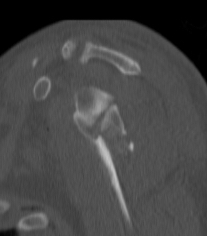

Type IA: Anterior glenoid rim fracture

Xray / CT

Type II: Fracture glenoid fossa that exits laterally

Definition

Transverse fracture through glenoid fossa

- inferior triangular fragment

- exits lateral border scapula